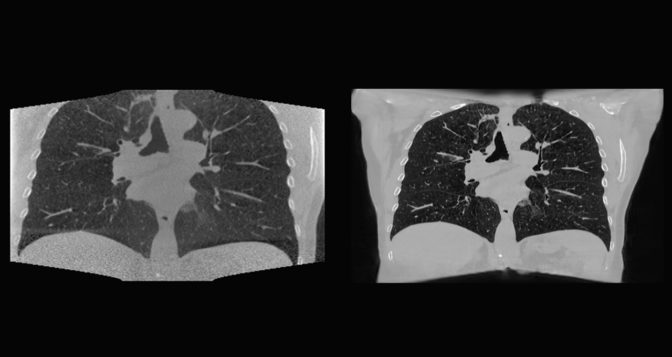

NKI’s AI model was previously trained on lower-resolution images. But with the higher memory capacity offered by NVIDIA AI Enterprise, its researchers could instead use high-resolution images for training. This improvement helps clinicians better target the size and location of a tumor every time a patient receives treatment.

Researchers at NKI used NVIDIA AI Enterprise, running on the HPE Synergy, a composable software system from Hewlett Packard Enterprise, to build deep learning models by combining the massive 2D and 3D data sources and AI to pinpoint the location of tumors before each radiotherapy treatment session.

“Doctors could use this solution as an alternative to CT scans on day of treatment to optimize the treatment plan to validate the radiotherapy plan,” said Jonas Teuwen, group leader at the Netherlands Cancer Institute.

Using NVIDIA AI Enterprise, Teuwen’s team in Amsterdam ran their workloads on NVIDIA A100 80GB GPUs in a server hosted in Silicon Valley. Their convolutional neural network was built in less than three months and was trained on less than 300 clinical lung CT scans that were then reconstructed and generalized to head and neck data.